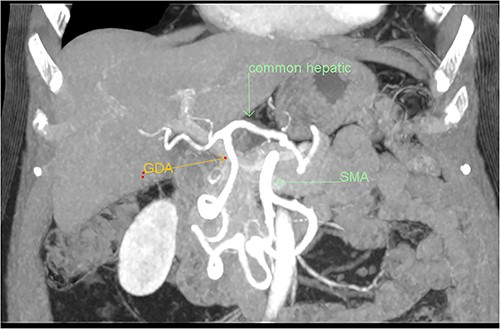

A multiphase CT of the pancreas had unexpected findings. There were no pancreatic masses on the arterial and portal phase study, and no paraaortic or mesenteric lymphadenopathy. The abnormal calcification seen on the previous study corresponded to a dilated vessel along the superior margin of the pancreatic body. This dilated vessel was an abnormal communication between a tortuous ecstatic gastroduodenal artery and the first branch of the SMA, a Buhler’s arc communication. The celiac axis origin was narrowed >90%. No other suspicious solid organ mass lesion was identified. Soft tissues were unremarkable (Figs 5–8).

Multiphase CT pancreas, coronal view: the gastroduodenal artery, off the common hepatic, communicating with the first branch of the SMA.

3D reconstruction demonstrating abnormal communication between the CA and SMA.